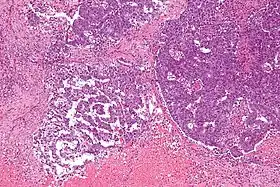

EST يمكن أن يكون له العديد من الأشكال بما في ذلك: شبكي، الأديم الباطن للجيوب الأنفية مثل، التكيسات الدقيقة، حليمي، الصلبة، غدي، السنخية، المحي polyvesicular، الملهبة وشبيه بالكبد.

الهيئات شيلر دوفال للأنسجة واصم ويتضمن شكل نمطي مثل جيب الأديم الباطن.